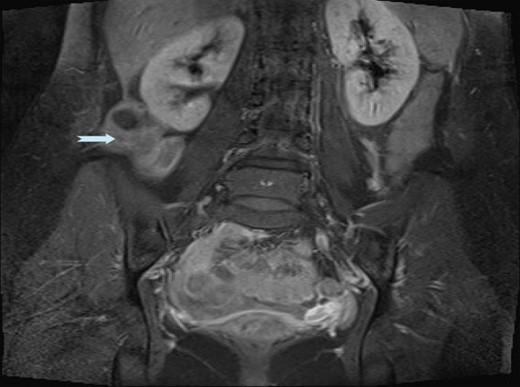

An ultrasound scan (USS) was performed and a 9 cm mass was demonstrated. A subsequent computer tomography (CT) scan confirmed the mass (Fig. 1) and raised the possibility that the mass may be a small bowel neuroendocrine tumour. The mass reported as separate from the appendix and caecum and no evidence of appendicitis. On the following day, the images were presented, the case was discussed at the colorectal multi-disciplinary team (MDT) meeting and a collective decision was made to perform a magnetic resonance imaging (MRI) scan which the patient underwent the following day. MRI was performed to specifically define the anatomy of the small bowel and its relation to the mass, as this was not clear on CT imaging. Ultimately, the MRI demonstrated a mass with vascular pedicle arising from the inferior aspect of the right hepatic lobe and the appearance raise the possibility of an exophytic liver lesion which has undergone torsion (Fig. 2). She was taken for a diagnostic laparoscopy the next day however given the size of the mass and the slim body habitus of the patient, a decision was made to convert to lower midline mini laparotomy.

MRI images demonstrating ALL with vascular pedicle attached to liver.

ALL may appear as an undetermined mass on imaging, however, visualization of the anatomic connection of the ALL to the liver can be appreciated through the use of CT or MRI. In our case the MRI was more sensitive than the CT scan in establishing the diagnosis. The presence of independent biliary drainage as well as arterial, venous and portal branches should arouse suspicion of this rare anomaly. In case of torsion the appearance might be more difficult because of the lack of visualization of the vascular pedicle. Enhanced CT scan usually shows vascularization defects, loss of normal architecture of liver parenchyma, and uncertain origin of the mass which may be confused with extrahepatic tumours of pancreatic, ovarian, or peritoneal origin or an acute inflammatory condition (e.g. cholecystitis and appendicitis). On ultrasonography, a twisted ALL appears as an hypoechogenic mass caused by congestion, and on colour Doppler ultrasonography, it appears to be without vascular supply.